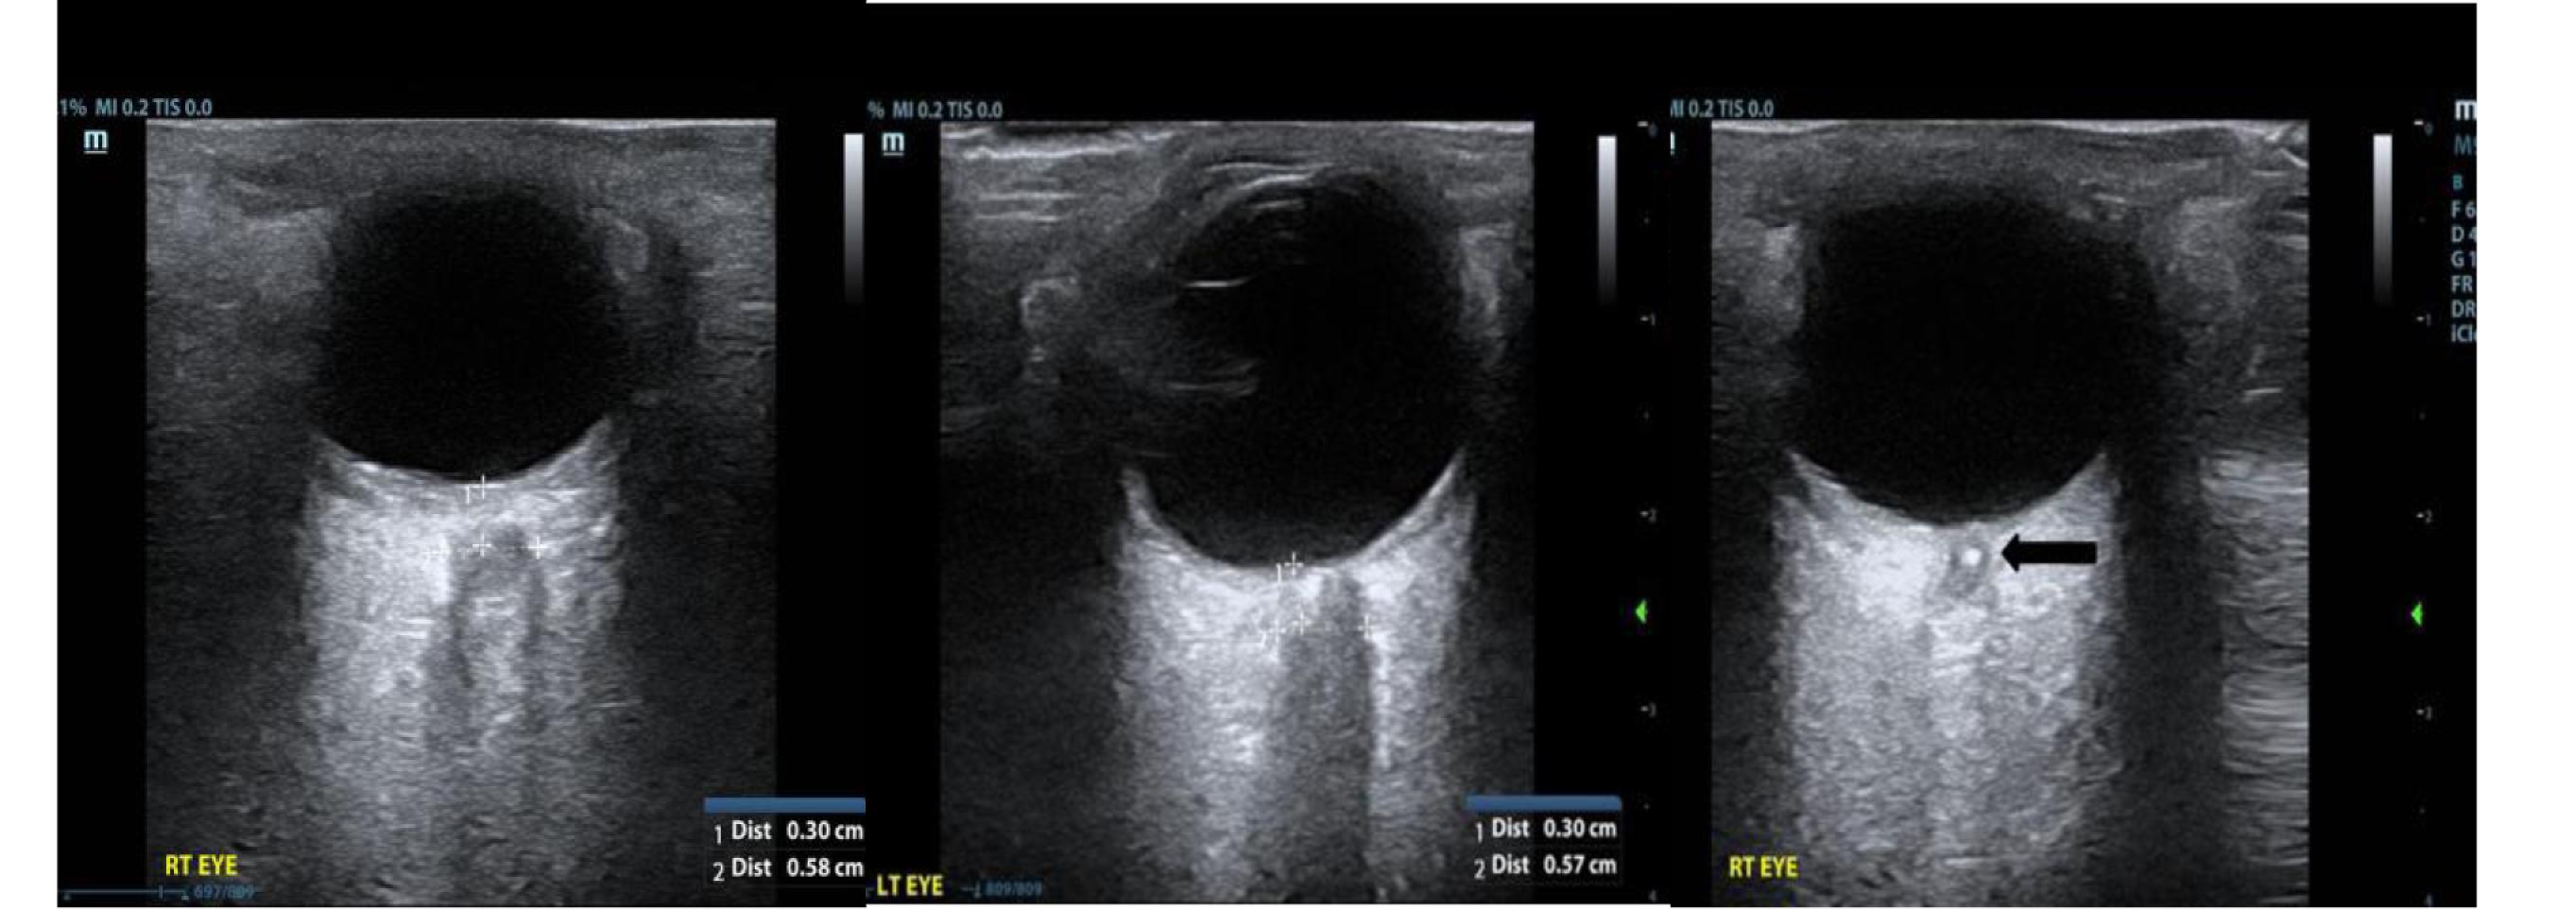

Arrowhead Regional Medical Center Colton, CA

115 Emergency Department Doppler Assessment of a Central Retinal Artery Occlusion: Case Report Duncan McGuire, Robert Calleja, Eric Pai, Amit Bahl

Alternativestohydrochloricacidinfusionsinclude ammoniumchlorideandargininemonohydrochloride, althoughthesearebothdependentonhepaticmetabolism.18 Finally,controlledhypoventilationhasbeenproposedasan optionforcriticallyillintubatedpatientswithsevere alkalosis.Whilenodataexiststosuggestspecifictargetsof minuteventilationorpCO2 inseveremetabolicalkalosis,a fewcasereportsmentionusingcontrolledhypoventilationto exaggeratethephysiologicrespiratorycompensationof alkalemiainmechanicallyventilatedpatients.14

Althoughlossofgastrointestinalsecretionsisoneofthe mostcommoncausesofmetabolicalkalosis,priorcase reportsofseveremetabolicalkalosiscausedbymistakenly intentionalprolongedgastrostomytubedrainagearenotin theliterature.Drainageorventingofagastrostomytube canbeatemporarytherapytotreatsymptomssuchas

fullnessorbloatingorincasesofobstruction 19;however, prolongeddrainageofgastrointestinalsecretionswithout addressingtheunderlyingproblemcanbedetrimentalto thepatient.

Thiscase,whichhighlightsfundamentalunderstandingof gastrointestinalandacid-basephysiology,demonstratesthe dangersofongoinglossofgastricsecretionsandmetabolic alkalosis.Itservesasanexampleofidentifyingthe underlyingcauseofalkalosisandsubsequent treatmentoptions.

TheauthorsattestthattheirinstitutionrequiresneitherInstitutional ReviewBoardapproval,norpatientconsentforpublicationofthis casereport.Documentationon file.

AddressforCorrespondence:ForrestTurner,MD,CarolinasMedical Center,DepartmentofEmergencyMedicine,1000BlytheBlvd., Charlotte,NC28203.Email: forrestturnermd@gmail.com

ConflictsofInterest:Bythe CPC-EM articlesubmissionagreement, allauthorsarerequiredtodiscloseallaffiliations,fundingsources and financialormanagementrelationshipsthatcouldbeperceived aspotentialsourcesofbias.Theauthorsdisclosednone.

Copyright:©2024Turneretal.Thisisanopenaccessarticle distributedinaccordancewiththetermsoftheCreativeCommons Attribution(CCBY4.0)License.See: http://creativecommons.org/ licenses/by/4.0/